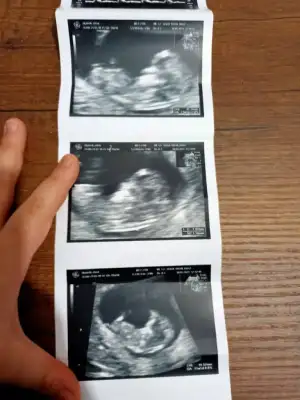

Merhaba arkadaslar,aslinda bebegimin cinsiyeti belli,dr.eşime kağıda yazıp verdi ama eşim pazar gunu surpriz yapacagi icin bana søylemiyor,sizin bi tahmininiz varmı?Merakdan çatliyorum.😄😊Eki Görüntüle 2848569

Emin olmadım ama sanki kız gibi geldi bana 🙈 en iyi 11 12 13 haftalar olmalı yada başka USG varsa paylaşın 🤗